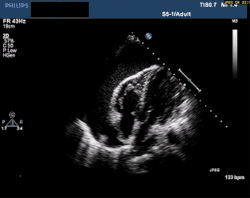

At the bedside, point-of-care echocardiography should be used.[22] This is non-invasive and can help diagnose the four types of shock.[24] Echocardiography can look for ventricular dysfunction, effusions, or valve dysfunction.[3][25] Measurement of the vena cava during the breathing cycle can help assess volume status.[22][24] A point-of-care echocardiogram can also assess for causes of obstructive shock. The vena cava would be dilated due to the obstruction. In pulmonary embolism, the right ventricle will be dilated. Other findings include paradoxical septal motion or clots in the right heart or pulmonary artery. Echocardiography can assess for pericardial effusion. In tamponade, collapse of the right atrium and ventricle would be seen due to pressure in the pericardial sac.[24]

A chest X-ray can rapidly identify a pneumothorax, seen as absence of lung markings. Ultrasound can show the lack of lung sliding. However, imaging should not delay treatment.[8] CT angiography is the standard of diagnosis of pulmonary embolism. Clots appear in the vasculature as filling defects.[18]